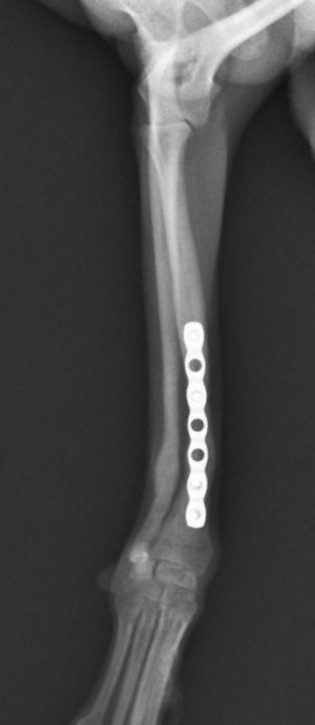

右前腕骨折のポメラニアンちゃんが来院されました。橈尺骨骨折は動物病院では一番よくある骨折です。ロッキングプレートであるTAITAN1.2で対応しました。治りも順調で元気に帰りました。よかったね。